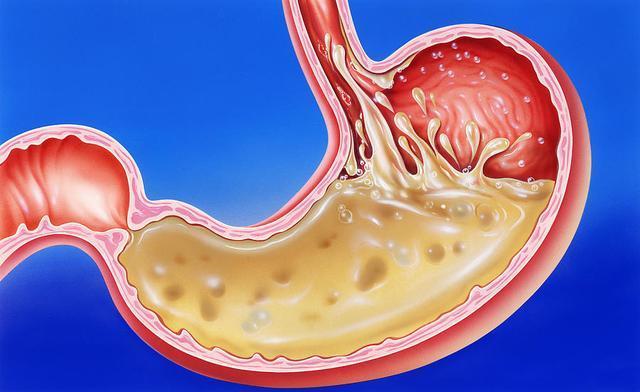

由於現代生活節奏比較快,人們在飲食上總是出現不規律的狀態,經常飢一頓飽一頓,暴飲暴食,其實這對胃是極其不利的,很容易造成胃部損傷,影響人體健康。胃作為消化的主要器官,如果出現健康問題,將會引起胃酸分泌過多、胃潰瘍等症狀。

胃酸是從胃液中分泌出來的一種鹽酸,能夠幫助人體消化食物,但胃酸要控制在一定的範圍之內,如果胃酸過少,會影響人體的消化,易引發營養不良等症狀;

胃酸分泌過多,會刺激到胃粘膜,導致胃出血以及口臭。對於胃酸引起的口臭,除了要養腸胃,還要做好這4件事,預防胃病口臭。